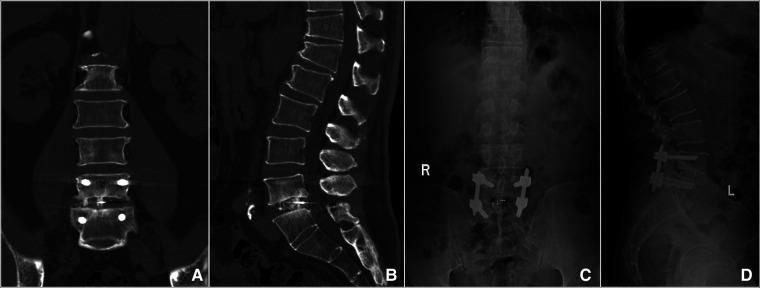

This study aims to investigate the effectiveness and feasibility of biportal endoscopic decompression, debridement, and interbody fusion, combined with percutaneous screw fixation for lumbar brucellosis spondylitis (LBS).

The data of 13 patients with LBS were retrospectively analyzed, who underwent biportal endoscopic decompression, debridement, and interbody fusion, combined with percutaneous screw fixation from May 2020 to June 2022. The patients' clinical data, the duration of operation, the estimated blood loss (including postoperative drainage), and complications were recorded. Clinical outcomes include serum agglutination test (SAT) measures Brucella antibody titer, erythrocyte sedimentation rate (ESR), C-reactive protein (CRP), the visual analog scale (VAS) scores of low back and leg, Japanese Orthopaedic Association (JOA) score, Oswestry Disability Index (ODI), American Spinal Injury Association neurological classification, and lordotic angle were analyzed. All patients were assessed using the modified Macnab criteria at the final follow-up. The intervertebral bone graft fusion was assessed using the Bridwell grading criteria.

The mean operation duration was 177.31 ± 19.54 min, and the estimated blood loss was 176.15 ± 43.79 ml (including postoperative drainage was 41.15 ± 10.44 ml). The mean follow-up period was 13.92 ± 1.5 months. SAT showed that the antibody titers of 13 patients were normal 3 months after the operation and at the final follow-up. ESR and CRP levels returned to normal by the end of the 3-month follow-up. VAS scores of low back and leg, JOA score, and ODI significantly improved after the operation throughout the follow-up period ( < 0.05). Based on the modified Macnab criteria, 92.3% showed excellent to good outcomes. One patient had only a percutaneous screw internal fixation on the decompression side due to severe osteoporosis. One case suffered a superficial incision infection postoperatively that healed with dressing change and effective antibiotic treatment. Bony fusion was obtained in all patients at the last follow-up, including 12 cases with grade I and 1 case with grade II, with a fusion rate of 92.31%.

Biportal endoscopic decompression, debridement, and interbody fusion, combined with percutaneous screw fixation is an effective, safe, and viable surgical procedure for the treatment of LBS.